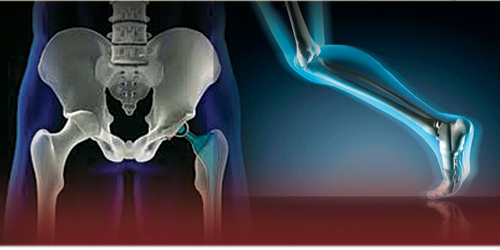

Arthroscopy & Joint Replacements

- Arthroscopic assessment & treatment of major joints.

- Joint reconstruction for complex ligament and tendon injuries.

- Total Knee Replacement (TKR) & Hip Replacement surgeries.